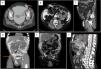

Two of the abdominal lumps were identified as hernias (Fig. 1A), another was identified as dialysate leakage through the catheter entry point (Fig. 1B), and in the fourth case, the leakage point was not visualized. Cases of genital edema were identified as dialysate leakage on 3 occasions (Fig. 1C and D) and as inguinal hernias on the fourth (Fig. 1E). In one of the ultrafiltration defect cases, a dialysate leak point could not be confirmed, and in the other, a pleuroperitoneal communication was demonstrated (Fig. 1F).

A: Abdominal bulge due to hernia (arrow). B: Leakage of dialysate through the subcutaneous route. C: Dialysate leakage due to persistence of the duct processus vaginalis. D: Leakage of the dialysate by dissection of planes from a small point of leakage (arrow). E: Genital edema due to bilateral hernias (arrows). F: Ultrafiltration failure due to peritoneal pleural leakage (arrow = vanishing point) (star = pleural effusion).